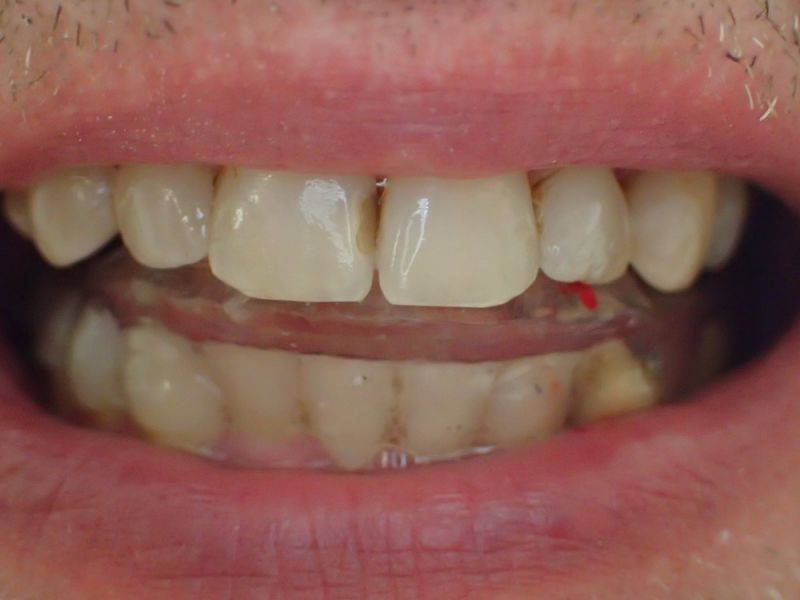

Der Patient hat von einem CMD Spezialisten in Bielefeld einen Aufbissbehelf erhalten. Den hat der Patient mit Zellstoff unterfüttert, weil der Aufbissbehelf so unterschiedlich hoch war, dass der Patient es vor Schmerzen mit dem Aufbissbehelf nicht ausgehalten hat.

2. Herstellung und Eingliederung eines adjustierten Aufbissbshelfs

Erkennbar ist die massive Abweichung der habituellen Bisslage von der neuromuskulär zentrierten Bisslage.